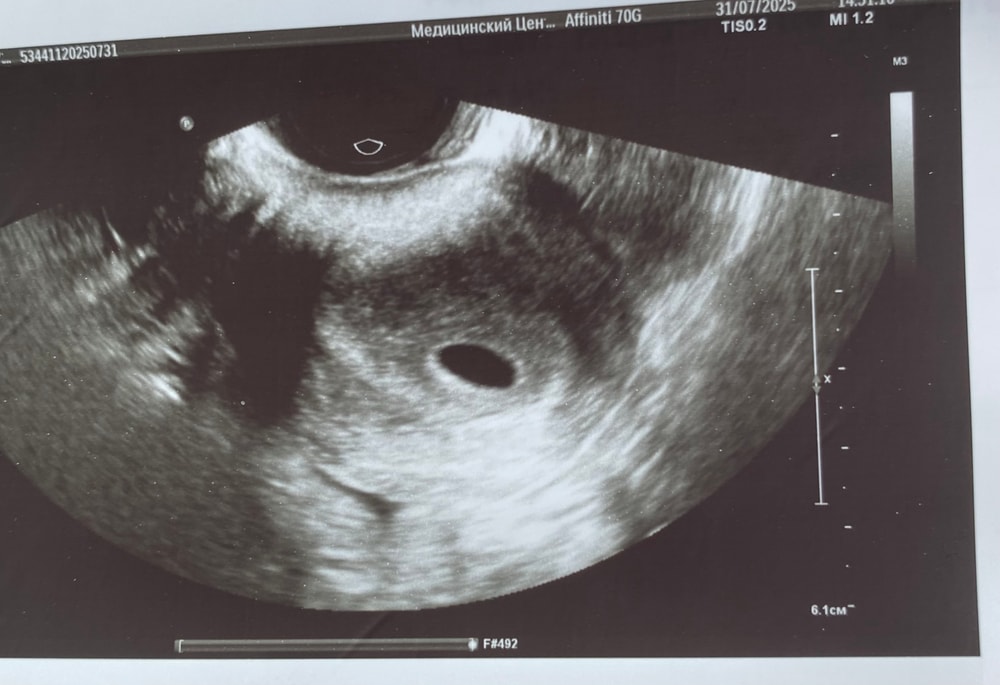

УЗИ 5 недель 0 дней

Сегодня ровно 5 недель или 23 ДПО.

На УЗИ нашли плодное яйцо в матке, СВДПЯ - 10 мм, но нет желточного мешка. Врач сказала, что при таком размере плодного яйца обычно уже бывает жм. Но срок у меня маленький, поэтому его, возможно, и нет. Сказала не волноваться и снова сделать УЗИ через 10 дней.